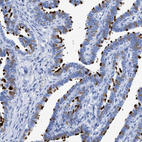

Immunohistochemistry analysis in human fallopian tube and cerebral cortex tissues using HPA016816 antibody. Corresponding RSPH1 RNA-seq data are presented for the same tissues.